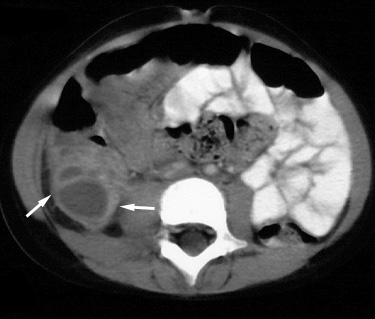

| Perforated appendicitis with an obstructing

appendicolith and a fluid-filled, dilated appendix. 13 year old girl presented with increasing right lower quadrant pain of one day's duration. |

![]() |

Figure 1. Contrast enhanced axial CT image in the upper pelvis demonstrates a calcified appendicolith (arrow) in the region of the appendiceal neck adjacent to the cecum (C). |

Figure 2. CT image obtained caudal to Figure 1 shows a dilated, fluid-filled, obstructed appendix (arrows). Sigmoid colon (S) and rectum (R) are seen posteriorly. |